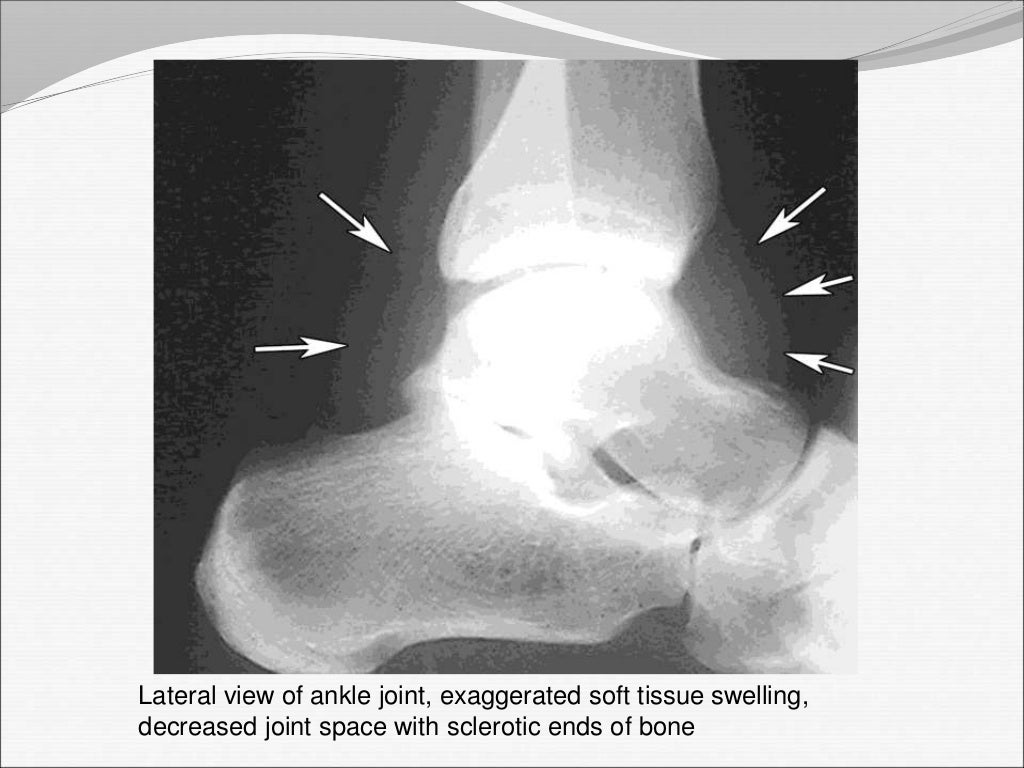

Septic arthritis Septic Arthritis Elbow X Ray The differential diagnosis of an acutely painful joint is broad and includes crystalline and inflammatory. The epidemiology, microbiology, clinical manifestations, diagnosis, differential diagnosis, and treatment of septic arthritis of. Oligoarticular septic arthritis is more likely to present with symptoms of systemic infection and more commonly affects the shoulder, wrist, and. Septic arthritis of the shoulder and elbow primarily affects individuals. Septic Arthritis Elbow X Ray.